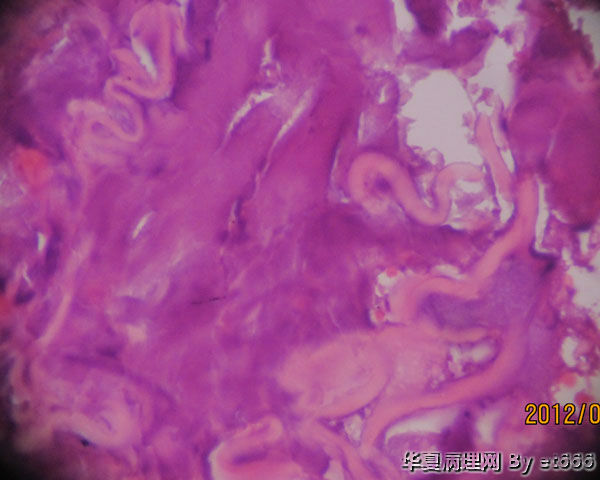

患者 75 腹股沟淋巴结活检 )送检软组织内可见片状干酪样坏死物,边缘有炎性肉芽组织,形态符合结核性病变。抗酸杆菌染色(-), 结核杆菌DNA检测(+)。在另一部位可见如图物质 不知是 .......请老师专家们赐教。

真菌菌丝?异物?其他?

有可能是隐球菌

会不会是寄生虫啊。照几张病变周边的反应性区域看看。

再传几张 。 其实我发报告的时候没有看见这些东西。后来有其他原因再看时发现这些物质的,可能这些物质颜色淡不显眼吧.

像是真菌

是的,而且是中空的。

考虑是寄生虫